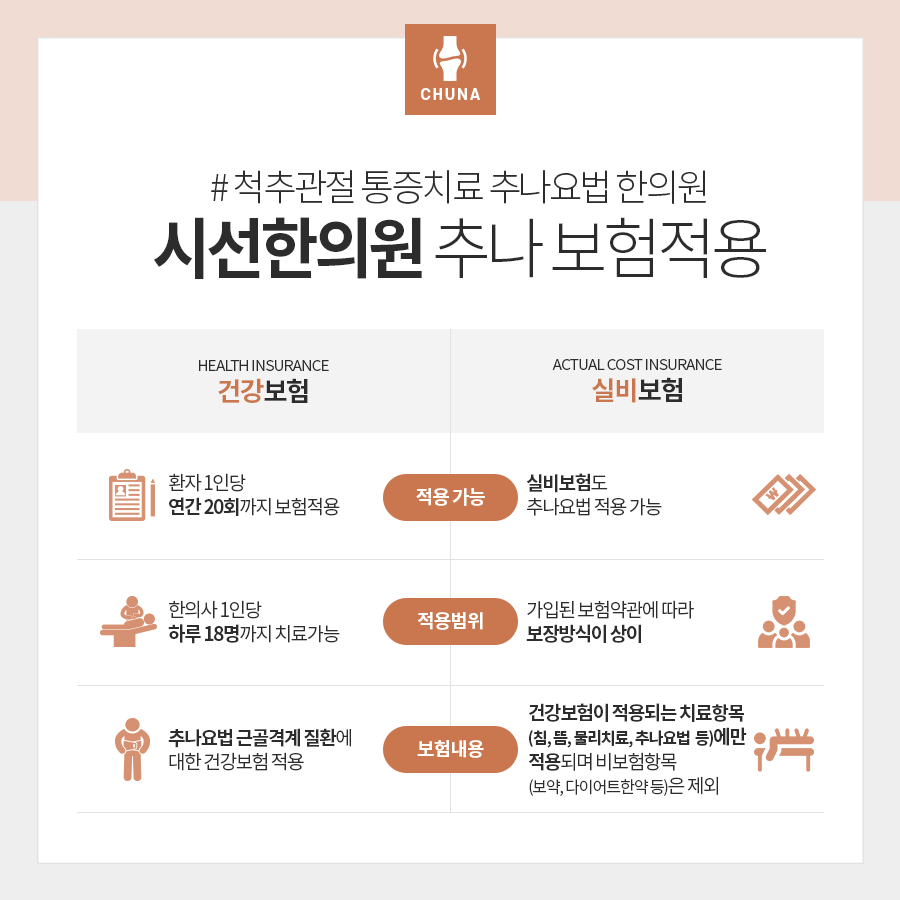

어깨가 아니더라도 근골격질환이 있는 경우에는 추종요법시 건강보험이 적용되며, 개인실비보험 약관이 어떠냐에 따라 건강보험과 실비보험이 동시에 적용될 수 있으므로 추종을 위해 치료를 고려하고 있는 경우 해당 사항에 대해서도 설명해 드리겠습니다.